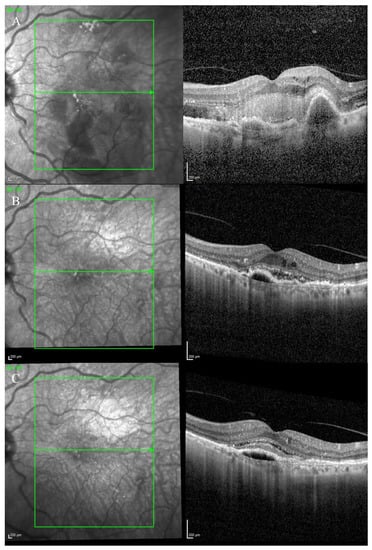

A 78-year-old female patient was referred to our department with nAMD in both eyes. She had a long history of different types of anti-VEGF intravitreal injections since 2012.

She showed features of BALAD in both eyes since the initial diagnosis was made. Her initial BCVA was 0.4 logMAR in both eyes.

The anterior segment examination was unremarkable in both eyes.

Fundus examination showed a macular yellowish elevated lesion in both eyes (Figure 6A,B). FAF revealed a hypoautofluorescent macular lesion (Figure 6C,D).

Figure 6.

Case 5. Multimodal imaging features of bacillary layer detachment (BALAD) in neovascular age-related macular degeneration patients in both eyes. (A,B) Optos Ultra-widefield colour shows a macular yellowish slightly elevated macular lesion. (C,D): Optos Ultra-widefield autofluorescence imaging shows a hypoautofluorescent macular lesion. (E) Heidelberg Spectralis optical coherence tomography shows a type 1 MNV with subretinal and intraretinal fluid and BALAD in the right eye. (F) Heidelberg Spectralis optical coherence tomography shows a type 1 MNV with subretinal fluid and BALAD in the left eye.

The OCT showed a type 1 MNV with a fibrovascular PED, subretinal fluid, and BALAD in both eyes (Figure 6E,F).

The OCTA scan confirmed the presence of MNV (Figure 7A,B).

Figure 7.

Case 5. Heidelberg Spectralis optical coherence tomography angiography shows a subretinal neovascular membrane in right (A) and left eyes (B).

Over the years, these features have shown improvement phases alternating to worsening ones.

The patient is still on treatment with anti-VEGF intravitreal injections (T&E regimen) for both eyes.

The BCVA has been stable throughout the treatment period. When last examined, it was 0.63 logMAR in the right eye and 0.32 logMAR in the left eye.